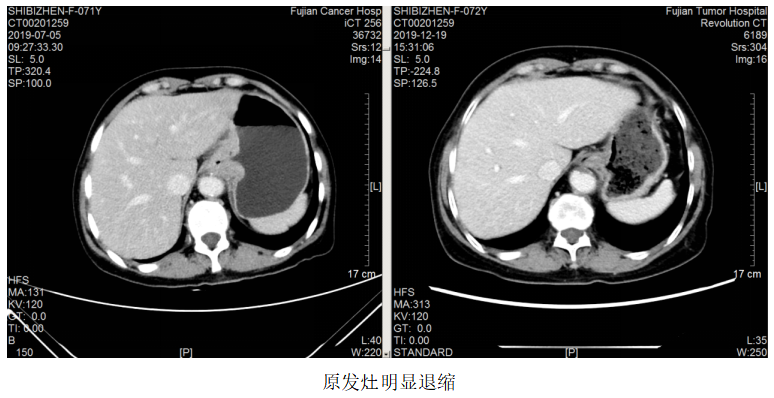

一线治疗:2019.7.12~10.24予FOLFOX方案(奥沙利铂110mg+左亚叶酸钙300mg+5-Fu 2.75)化疗8周期,曲妥珠单抗220mg靶向治疗7次。

疗效评估:PR。

维持治疗:2019.11.6~2022.03.02予方案“卡培他滨+曲妥珠单抗q3w”维持治疗。

2021.5.18开始患者因经济原因改予汉曲优治疗至今,肿瘤进一步退缩,疗效评估PR。

该例患者为胃癌脑转移。脑转移患者的抗HER2治疗一直存在着大分子单抗和小分子TKI之争。有研究显示,由于脑肿瘤部位的血脑屏障受损,通透性要高于正常脑组织,因此曲妥珠单抗可以透过血脑屏障到达病灶部位,尤其是一些接受过脑放疗的病人更是如此。对这例患者,初诊时即存在脑转移,选择了曲妥珠单抗+化疗作为一线治疗,配合脑部放疗,达到PR效果,而后新增脑转移灶,再次放疗,继续曲妥珠单抗治疗,仍达到PR效果,患者前期予赫赛汀,后期因经济原因改予汉曲优,肿瘤依然进一步控制,患者OS>28个月。

本例报道为HER2阳性胃癌患者,初诊时已经出现脑转移。由于曲妥珠单抗是一个大分子单克隆抗体,其通过血脑屏障的能力有限,但一些学者认为如果发生肿瘤脑转移,脑肿瘤部位的血脑屏障受损,通透性要高于正常脑组织,因此曲妥珠单抗可以透过血脑屏障到达病灶部位,尤其是接受过脑放疗的患者。因此对于HER2阳性胃癌脑转移患者,推荐使用含曲妥珠单抗的抗HER2治疗方案,本例患者初诊即存在脑转移,选择了曲妥珠单抗+FOLFOX作为一线治疗,配合脑部放疗,达到PR效果后采用卡培他滨+曲妥珠单抗维持治疗,停药3个月新增脑转移灶,再次放疗,继续选用曲妥珠单抗联合卡培他滨治疗,仍达到PR效果,获得了较好的疗效。